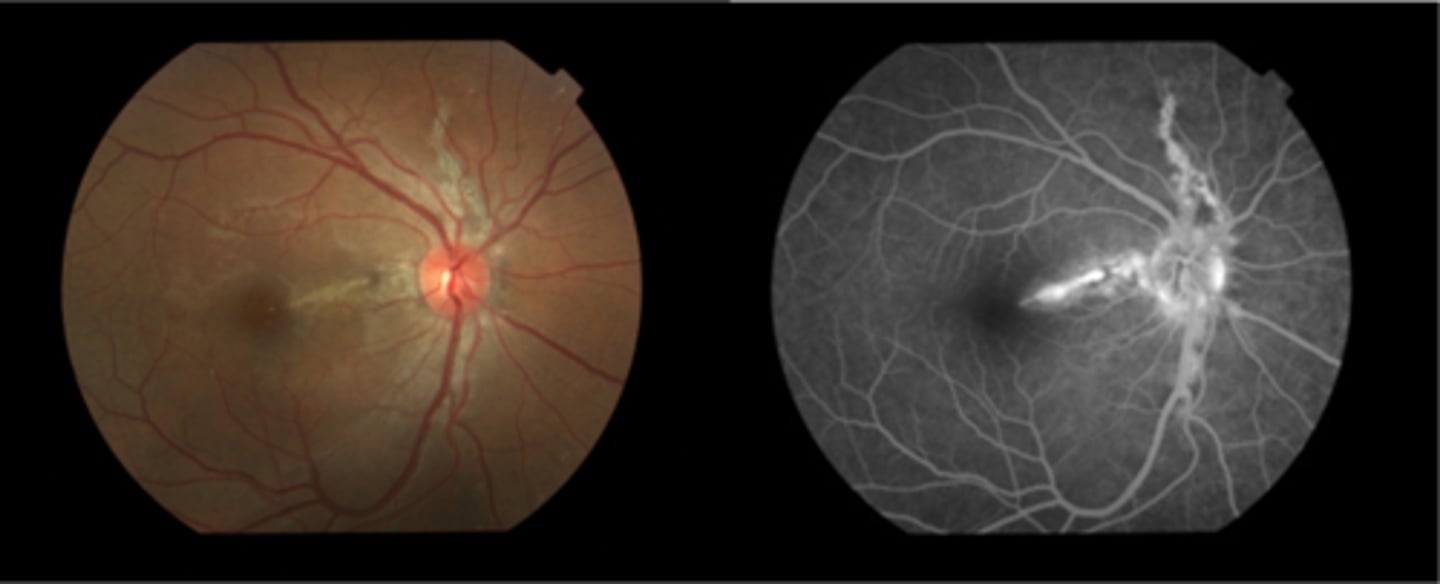

What are angioid streaks and what type of atrophy do they lead to?

breaks in Bruch's membrane in a radiating fashion emanating from the ONH = leads to RPE, PR's, choriocapillaris atrophy

What causes angioid streaks?

weakened, calcified Bruch's membrane, often in connective tissue disease = bilateral

What are the 5 CT diseases associated with angioid streaks?

PEPSI:

Pseudoxanthoma elasticum

Ehlers-Danlos syndrome

Paget's disease (of bone)

Sickle cell disease (and other hemoglobinopathies)

Idiopathic

THINK: Angie likes to drink PEPSI

How do angioid streaks affect VA?

often asymptomatic as does not involve macula

What are 2 possible complications of angioid streaks?

CNV

choroidal rupture

How do we manage angioid streaks?

educate on potential CNV or choroidal rupture, esp with injury = polycarbonate, reduced contact sports

Amsler for home monitoring

refer for CT disease workup if not already diagnosed

How does angioid streaks appear on IVFA?

hyperF bc loss of RPE = can see choroid better

How does angioid streaks appear on FAF?

hypoAF bc RPE loss/damage

What ONH finding is sometimes seen with angioid streaks?

disc drusen